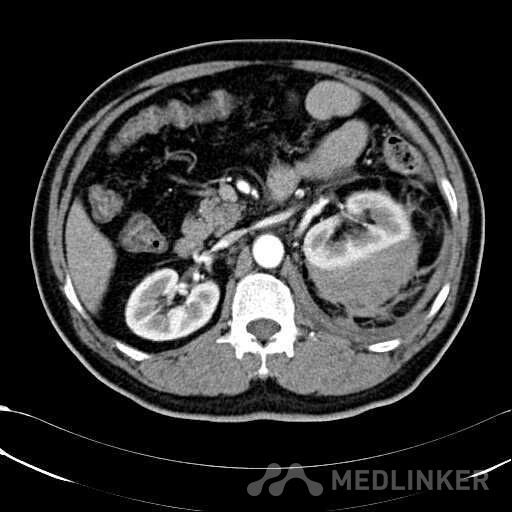

患者是54岁男性 主 诉: 突发左腰部疼痛3小时。 现病史: 缘于入院前3小时患者无明显诱因出现左腰部剧烈疼痛,无向他处放射,与活动及体位无明显关系,伴有腹胀、恶心、呕吐,无头痛、头晕,无人事不省、口吐白沫,无胸闷、胸痛、咯血,无发热、畏冷、寒战,大小便未解,肛门无停止排气,遂就诊我院,查“泌尿系彩超:左肾实质及不均质回声区,范围约9.4*4.1cm,界不清,内未见明显血流信号”,为进一步治疗,门诊拟“左肾占位”收住入院,发病以来,患者精神欠佳,未进食,大小便如前述,体重无明显改变。 患有“高血压病”7年,规则服药治疗(具体不详),监测血压情况不详。 T: 36.5 ℃ P: 65 次/分 R: 20 次/分 BP: 154/94 mmHg 双肾区皮肤无红肿、破溃及隆起,双肾肋下均不能被触及,左侧肾区叩击痛明显,右侧肾区无叩击痛,双侧肾区未闻及血管杂音。膀胱区无隆起,无压痛,耻骨上膀胱区叩诊空虚。外生殖器发育正常。 2016-04-12 泌尿系彩超:左肾实质及不均质回声区,范围约9.4*4.1cm,界不清,内未见明显血流信号。 04-12血常规:血红蛋白 151 g/L,白细胞 16.80 10^9/L,中性粒细胞百分比 84.90 %。急诊生化:白蛋白 39.8 g/L,葡萄糖 9.46 mmol/L。